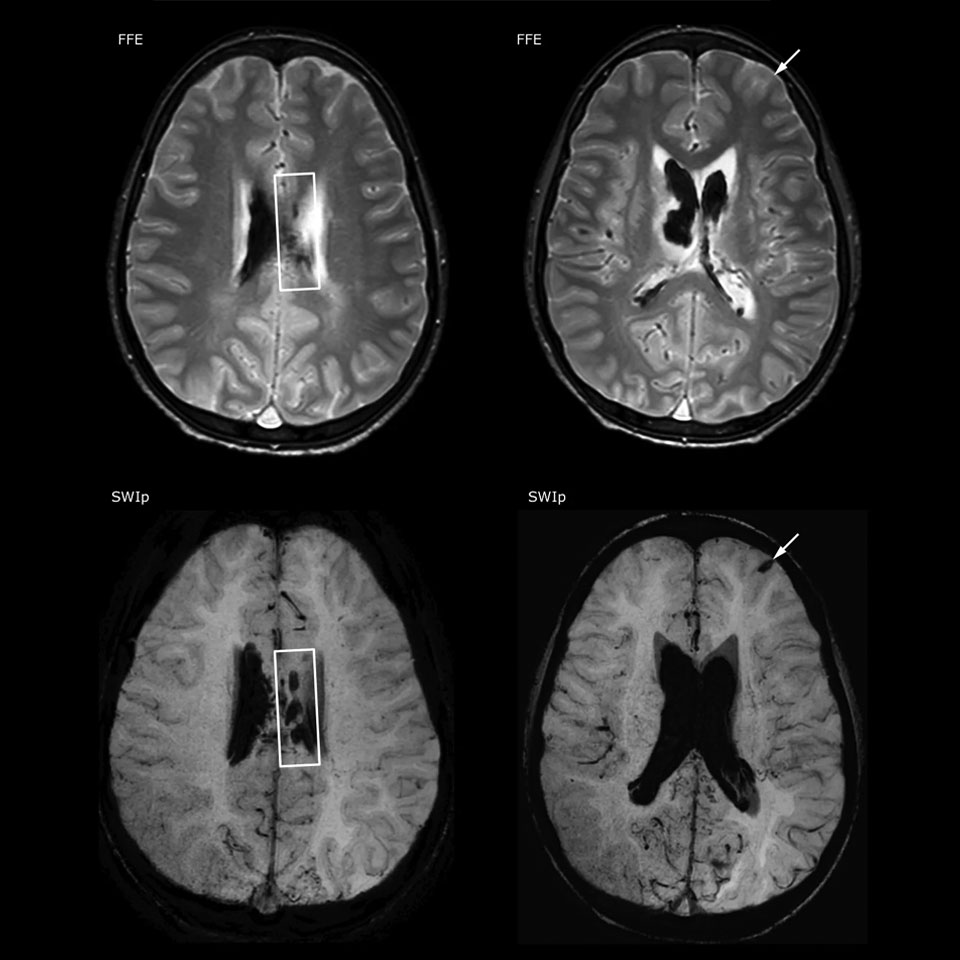

SWIp supports diagnostic confidence in traumatic brain injury

The value of susceptibility weighted imaging in visualizing brain injury is well documented. The Philips multi-echo SWIp technique provides fast susceptibility weighted imaging with enhanced susceptibility contrast and high resolution.

“Pediatric imaging is not without its challenges,” Dr. Miller says. “Since our patients are often very small, we need very high-resolution imaging. In cases of brain injury, we need to obtain information quickly so the treating clinicians can make decisions on care. We rely on high resolution and robust imaging capabilities, and SWIp provides that.”

“SWIp helps us identify blood or blood products, calcification, and diseases that affect the vascular system,” says Dr. Miller. “In children with traumatic brain injuries, it highlights areas that are injured, better than some of the previous techniques that we were using. These children often have micro-injuries that cause small amounts of blood or tissue damage. Adding SWIp helps us to better characterize the extent and nature of the injury. Having characterized an injury to the extent of what’s possible supports our diagnostic confidence.”

Full adoption after initial comparison

“I would definitely recommend other users to implement SWIp. We initially added the SWIp sequence following a lot of support for its utility in the literature. Then we directly compared SWIp to the 2D gradient echo sequences that we were using. After a good amount of clinical experience in seeing its benefits, we were confident to replace the old sequences with SWIp. It gives us a better assessment of the physiological processes of the brain that were less apparent on our previous imaging sequences,” says Dr. Miller. “SWIp is now a routine sequence for imaging traumatic brain injury patients at PCH, and it’s episodically added for patients who have intracranial vascular abnormalities.”

“I believe SWIp is rapidly becoming the standard in imaging traumatic brain injury, because of its high sensitivity to venous blood products. SWIp may even help attract patients; our neurosurgeons often ask to have the patients imaged on our scanners with highly sensitive techniques like SWIp. There’s also a growing application of SWI sequences in other vascular abnormalities because of the possibilities around physiological assessment of the brain than just a standard structural imaging.”